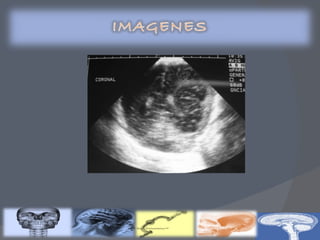

Recién nacidos con factores de riesgo : Prematuros Síntomas neurológicos Condiciones de riesgo  USG TRANSFONTANELAR (Primeros 5 días)

Clasificación de Volpe por ultrasonido transfontanelar Clasificación de Papile por tomografía axial computarizada Gravedad de la HIV Descripción GRADO I Hemorragia de la matriz germinal mínima(<10% del área ventricular) GRADO  II Hemorragia del área ventricular de 10 a 50% GRADO  III Hemorragia del área ventricular >50% Hemorragia intracerebral u otra lesión parenquimatosa Gravedad de la HIV Descripción % de HIV GRADO  I Hemorragia de la matriz germinal 40 GRADO II Hemorragia con tamaño normal de los ventrículos 30 GRADO III Hemorragia  con dilatación ventricular 20 GRADO IV Hemorragia ventricular, más parenquimatosa 10

GRADO 1 La hemorragia está localizada únicamente en la matriz germinal subependimaria GRADO 2 Contenido de sangre intraventricular que ocupa menos del 50% del área ventricular en una proyección parasagital GRADO 3 La sangre ocupa un área mayor del 50%, distendiendo el ventrículo Cuando existe una hemorragia intraventricular masiva que sobredistiende de forma muy importante los ventrículos laterales y, en general, todo el sistema ventricular está ocupado:tercer y cuarto ventrículos y espacio subaracnoideo de fosa posterior (cisterna magna)

Recién nacidos confactores de riesgo : Prematuros Síntomas neurológicos Condiciones de riesgo USG TRANSFONTANELAR (Primeros 5 días)

Clasificación de Volpepor ultrasonido transfontanelar Clasificación de Papile por tomografía axial computarizada Gravedad de la HIV Descripción GRADO I Hemorragia de la matriz germinal mínima(<10% del área ventricular) GRADO II Hemorragia del área ventricular de 10 a 50% GRADO III Hemorragia del área ventricular >50% Hemorragia intracerebral u otra lesión parenquimatosa Gravedad de la HIV Descripción % de HIV GRADO I Hemorragia de la matriz germinal 40 GRADO II Hemorragia con tamaño normal de los ventrículos 30 GRADO III Hemorragia con dilatación ventricular 20 GRADO IV Hemorragia ventricular, más parenquimatosa 10

GRADO 1 Lahemorragia está localizada únicamente en la matriz germinal subependimaria GRADO 2 Contenido de sangre intraventricular que ocupa menos del 50% del área ventricular en una proyección parasagital GRADO 3 La sangre ocupa un área mayor del 50%, distendiendo el ventrículo Cuando existe una hemorragia intraventricular masiva que sobredistiende de forma muy importante los ventrículos laterales y, en general, todo el sistema ventricular está ocupado:tercer y cuarto ventrículos y espacio subaracnoideo de fosa posterior (cisterna magna)